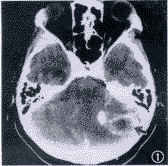

例3 患者44岁, 因双侧卵巢浆液性乳头状囊腺癌,于1993年4月6日接受子宫、双侧附件、大网膜切除和阑尾切除术。术后残留癌直径>2cm。临床病理分期为Ⅲc期,G2。术后采用PAC方案化疗9个疗程。化疗后行二次探查术和盆腔淋巴结清扫术,又行化疗3个疗程。第1次手术后临床无病变期26个月,1993年8月可疑盆腔复发,给予顺铂、吡喃阿霉素和环磷酰胺方案化疗3个疗程。第1次术后38个月因卵巢癌结肠转移(直径2.5cm),行第3次手术,切除部分乙状结肠和直肠。术后残留癌直径<2cm。化疗方案选择泰素和卡铂治疗6个疗程。此后定期随诊。1997年9月患者因剧烈头痛渐进性加重3周,行CT检查,发现小脑转移灶(图1)。于第1次术后53个月,行开颅手术切除小脑延髓池肿瘤6cm×6cm×5cm,病理报告为卵巢癌脑转移(图2)。术后采用威猛26 和甲基环己亚硝脲方案化疗11个疗程(剂量同例2,间隔6周1次)。化疗第1,2疗程之间患者接受了全颅照射,化疗半年和1年后再次行脑CT检查,无转移灶存在(图3)。脑转移后存活19个月。

图1 脑CT检查显示,左侧小脑转移灶3 cm×2 cm,转移灶周围脑组织水肿